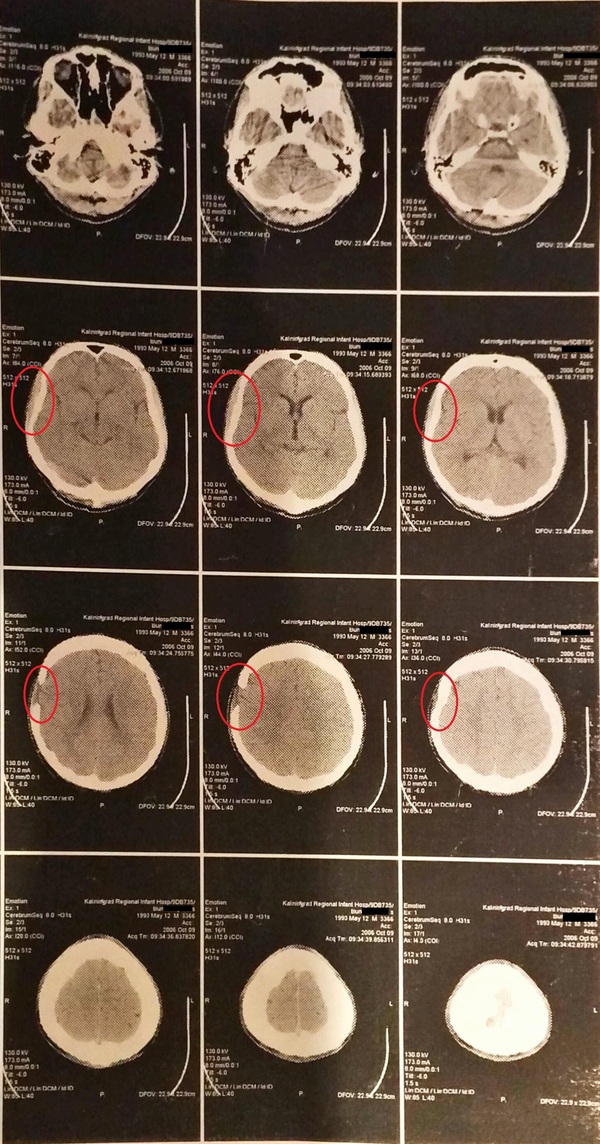

МРТ - красным обвел пробоину в борту